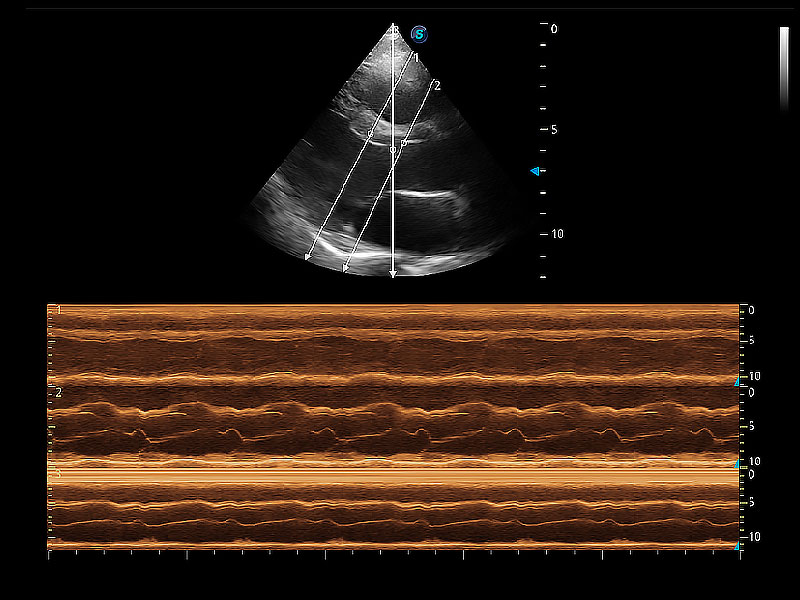

• AMM 解剖M型

通過360度任意調(diào)節(jié)3條M型取樣線,在同一心動周期上觀察心臟不同位置的運(yùn)動曲線,得到準(zhǔn)確的心功能測量數(shù)據(jù),有效評估心肌運(yùn)動及左心室功能。

(貓)二尖瓣M型